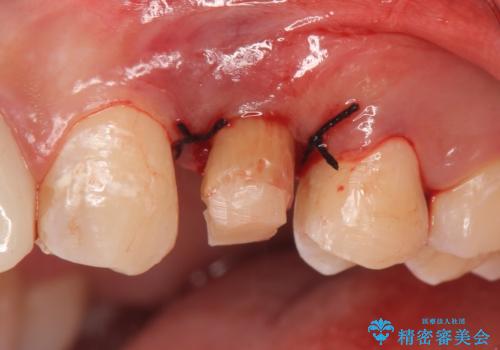

左上4の補綴物を除去したところ縁下歯質だったため、歯牙の挺出を提案し行いました。

挺出終了後は歯肉切除および骨外科により歯周組織を整え、オールセラミッククラウンによる補綴を行いました。